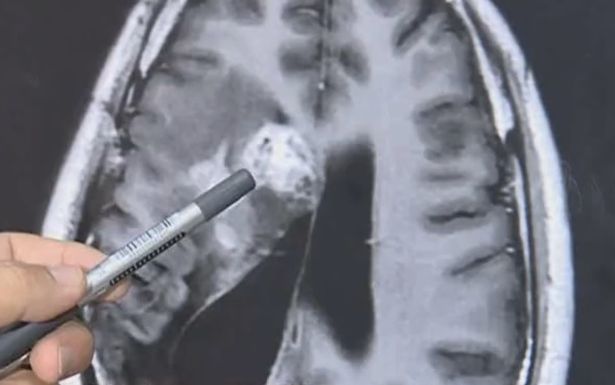

Sự việc xảy ra với một bệnh nhân tên Wang Lei tại Trung Quốc. Ông luôn cảm thấy những cơn đau đầu trong suốt nhiều năm nay. Khi đi khám, người ta mới phát hiện trong đầu của ông là một con sán dây dài tới 12cm.

Con sán dây sống trong não bệnh nhân.

Theo Mirror, một người đàn ông bị nhiễm sán dây dài 12cm lưu trú trong não và ăn não một cách từ từ trong suốt 15 năm qua.

Wang Lei bắt đầu cảm thấy đau phía bên trái đầu từ năm 2004, và sức khỏe không ngừng giảm sút kể từ đó.

Nhiều chuyên gia và bác sĩ từng nghi Wang bị u não. Trải qua nhiều năm chữa trị, tình trạng của người đàn ông Trung Quốc tiếp tục xấu đi, thỉnh thoảng bị co giật và ngất.

Ảnh chụp CT não của Wang.

Năm 2018, các bác sĩ phát hiện một con sán sống trong não bệnh nhân. Ở thời điểm đó, các bác sĩ chỉ định biện pháp chữa trị không phẫu thuật vì ký sinh trùng nằm ở khu vực nhạy cảm, rất khó phẫu thuật.

Đến nay, sán dây vẫn sống trong não Wang nên các bác sĩ ở bệnh viện tỉnh Quảng Đông phải phẫu thuật mở hộp sọ. Ca phẫu thuật kéo dài 2 giờ kết thúc tốt đẹp khi các bác sĩ gắp được con sán dây, chủ yếu ký sinh ở chó mèo, ra ngoài.

Bác sĩ Gu nói với truyền thông địa phương: “Ca phẫu thuật rất nguy hiểm. Sán dây không ngừng di chuyển trong não bệnh nhân, nhưng nếu không phẫu thuật, nó có thể đe dọa tính mạng bệnh nhân”.